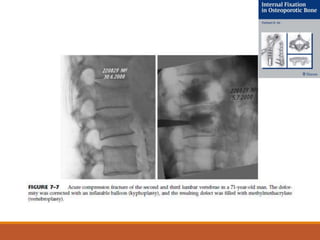

CIFOPLASTIA:

COMPLICACIONES:

VERTEBROPLASTIA VS